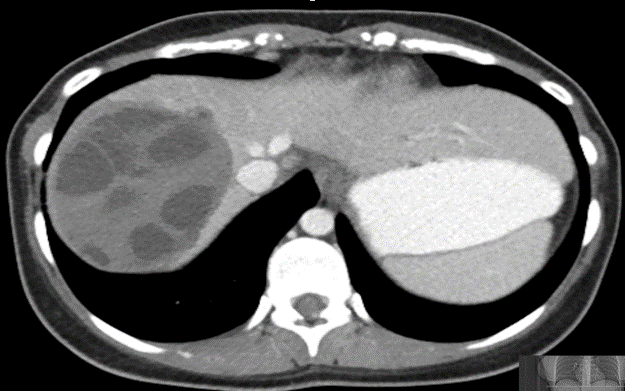

CASE 3 – A 23-year-old woman presents with 3 weeks of right upper quadrant (RUQ) pain associated with early satiety. The patient has no significant past medical history. She was born in Iraq and migrated to Australia from Syria 2 years prior to presentation. Preliminary blood results demonstrate moderate liver function test (LFT) derangement.

EXPLANATION -The case demonstrates classical appearance of a hepatic hydatid cyst. There is a well-defined rounded lesion in right lobe of liver with multiple small daughter cysts within. The fluid in the cysts can be of variable density depending on the proteinaceous contents (more protein = more dense). The thick internal septae can give a “spoke wheel” appearance as in this case. Curvilinear calcifications represents the inactive stage of the disease.

Hydatid diseases a parasitic zoonosis, caused by the larval stages of the Echinococcus granulosus .

- E. granulosusis found worldwide, however the highest rates of infection are seen in the Mediterranean and Middle Eastern regions, North Africa and South America.

- Hydatid cyst can occur anywhere in the body, the most commonly affected organ is the liver (76% of cases), followed by lung (15%) and spleen (5%).

- Classically there is a large ‘parent cyst’ which contains numerus peripheral ‘daughter cysts’.

- Humans are infected by eating the eggs of the tapeworm E. granulosus, by either eating contaminated food or through contact with dogs.

- The ingested embryos invade the intestinal mucosal wall, enter the portal circulation and develop cysts in the liver.

- Treatment options ; Surgical excision, PAIR (Puncture, Aspiration, Injection of protoscolicidal agent and Re-aspiration), Anti-helminthic agent (e.g. albendazole, mebendazole), Observation only – for inactive and silent cysts